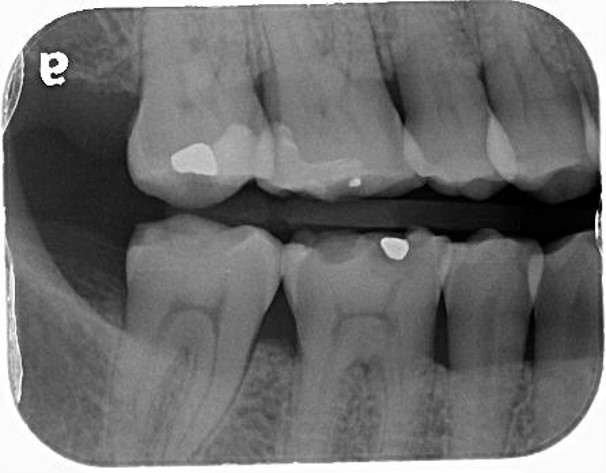

治療前,牙髓仍完整